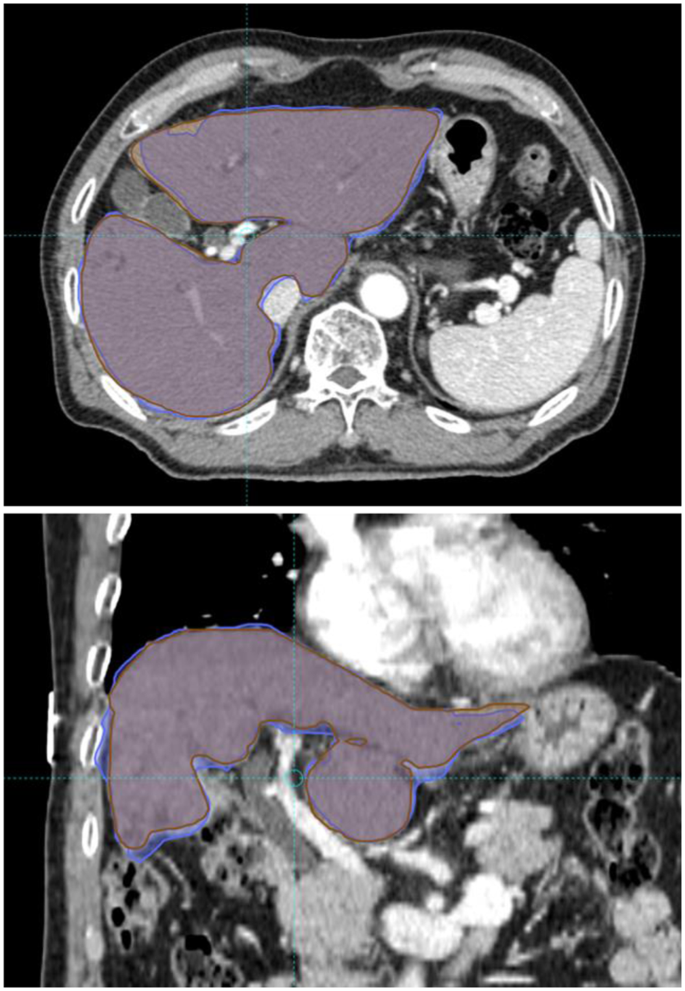

DIR was performed in all patients, and an example DIR is presented in Fig. 1. Mean Dice similarity coefficient (DSC) index value was 0.93 with a standard deviation of 0.03. The DSC index value was >0.9 in 79 (92.9%) registrations, with a value < 0.85 in one registration. The DSC index of rigid registration (single transformation vector for all voxels) was always inferior to that of DIR. DSC indices of DIR and rigid registration are presented in Fig. 2.

An example of deformable image registration. Liver contours were manually drawn on each computed tomography (CT) simulation image. The liver contour on the first CT simulation was deformed and registered onto the second CT image. The Dice similarity coefficient (DSC) was calculated between manually drawn liver contours in second CT simulation (brown) and the deformed contour from first CT simulation (blue). The DSC value of this patient was 0.94.